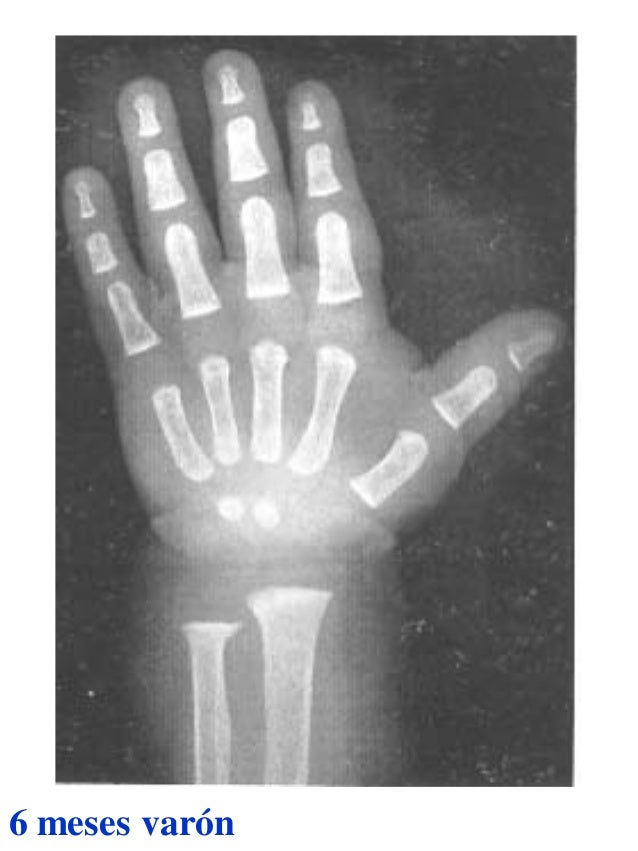

Tablas De Greulich Y Pyle The standards established by greulich and pyle, undoubtedly the most popular method, consist of two series of standard plates. The standards established by greulich and pyle, undoubtedly the most popular method, consist of two series of standard plates. El documento lista las edades. This systematic review summarizes the. The greulich and pyle method is one of the two main ways to assess the bone age of children. Both main methods of bone age. Scribd is the world's largest social reading and publishing site. 153 recomendaciones • 616,869 vistas. Atlas greulich y pyle | pdf | descarga gratuita. The greulich and pyle atlas is used to estimate the age of children and adolescents. The radiographic atlas of skeletal development of the hand and wrist by ww greulich and si pyle is a classic radiological.

Atlas greulich y pyle Tablas De Greulich Y Pyle The standards established by greulich and pyle, undoubtedly the most popular method, consist of two series of standard plates. Atlas greulich y pyle | pdf | descarga gratuita. Scribd is the world's largest social reading and publishing site. 153 recomendaciones • 616,869 vistas. The radiographic atlas of skeletal development of the hand and wrist by ww greulich and si pyle. Tablas De Greulich Y Pyle.